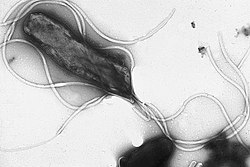

| Electron micrograph of H. pylori possessing multiple flagella (negative staining) | |

The first virulence factor of Helicobacter pylori that enables colonization is its flagellum.[87] H. pylori has from two to seven flagella at the same polar location which gives it a high motility. The flagellar filaments are about 3 μm long, and composed of two copolymerized flagellins, FlaA and FlaB, coded by the genes flaA, and flaB.[30][77] The minor flagellin FlaB is located in the proximal region and the major flagellin FlaA makes up the rest of the flagellum.[88] The flagella are sheathed in a continuation of the bacterial outer membrane, which gives protection against the gastric acidity. The sheath is also the location of the origin of the outer membrane vesicles that give protection to the bacterium from bacteriophages.[88]